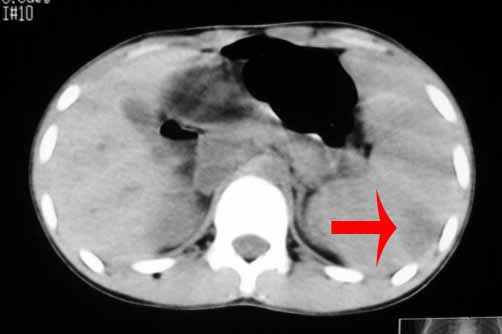

以下是引用zhangzhongshou在2007-5-22 21:04:00的发言:[br]1、脾肿大[br]2、脾脏低密度影,血管瘤?脾梗塞不能除外,建议增强扫描。

以下是引用dyqct在2007-5-22 20:45:00的发言:[br]巨脾,可疑梗塞,建议增强、查血象进一步检查

以下是引用liuyue在2007-5-23 7:57:00的发言:[br]腹主动脉周多个肿大淋巴结,脾大伴三角形低密度影,肠腔积气,考虑:1淋巴瘤2脾大伴梗塞3肠腔积气(肿大淋巴结压迫所致)